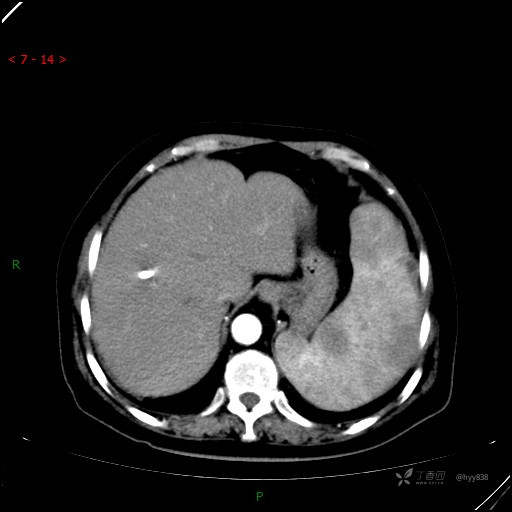

动脉期